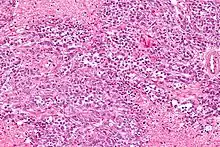

Cancer

Hypercalcemia of malignancy (cancer) is due to a variety of mechanisms. The two most common are humoral hypercalcemia of malignancy and local osteolytic hypercalcemia due to bony metastasis. Humoral hypercalcemia of malignancy involves the tumor releasing a hormone which increases calcium mobilization (most commonly parathyroid hormone-related protein (PTHrP)) into the circulation.[22] PTHrP acts similarly to parathyroid hormone in that it binds to the parathyroid hormone 1 receptors on the kidneys and bones and causes an increased tubular reabsorption of calcium and activation of osteoclast activity, respectively.[22] Osteoclasts are a type of bone cell which cause bone resorption, releasing calcium into the bloodstream. PTHrP also acts by activating rank ligand and inhibiting osteoprotegerin which activates nuclear factor kappa B, which causes further activation of osteoclast activity.[22] The combination of PTHrP driven osteoclast activation and calcium reabsorption by the kidneys causes hypercalcemia associated with malignancy (humoral type).[22]

Another mechanism in which cancer causes hypercalcemia is via local osteolysis due to metastasis to bone.[22] Tumor bone metastasis releases local cytokines including IL-6, IL-8, IL-11, interleukin-1 beta, TNF alpha and macrophage inflammatory protein. These cytokines activate osteoclasts and inhibit osteoblasts (the cell type responsible for laying down new bone) via the rank ligand pathway leading to bone resorption and calcium release into the bloodstream.[22] The massive release of calcium from bone metastasis and osteoclast activation usually overwhelms the kidney's ability to secrete calcium, thus leading to hypercalcemia.[22]

Hypercalcemia of malignancy may also occur due to tumor production of Vitamin D or parathyroid hormone. These causes are rare and constitute about 1% of all causes of hypercalcemia of malignancy.[22]

Hypercalcemia of malignancy usually portends a poor prognosis, and the medial survival is 25–52 days of its development.[22] It has an incidence of 30% in those with cancer, and the prevalence is estimated to be about 2-3% in the United States.[22]

Common cancer types that are associated with hypercalcemia of malignancy include:

- Solid tumor with metastasis via local osteolytic hypercalcemia: which can be due to any tumor that metastasizes to the bone. But common causes include breast cancer, lung cancer, kidney cancer, and myeloma or lymphoma of the bone[22]

- Solid tumor with humoral mediation of hypercalcemia: lung cancer (especially squamous cell tumors, a type of non-small cell lung cancer), squamous cell cancers of the head and neck, kidney cancer or other urothelial cancers, and breast cancer.[22]

- Hematologic cancers: including multiple myeloma, lymphoma, leukemia

- Ovarian small cell carcinoma of the hypercalcemic type